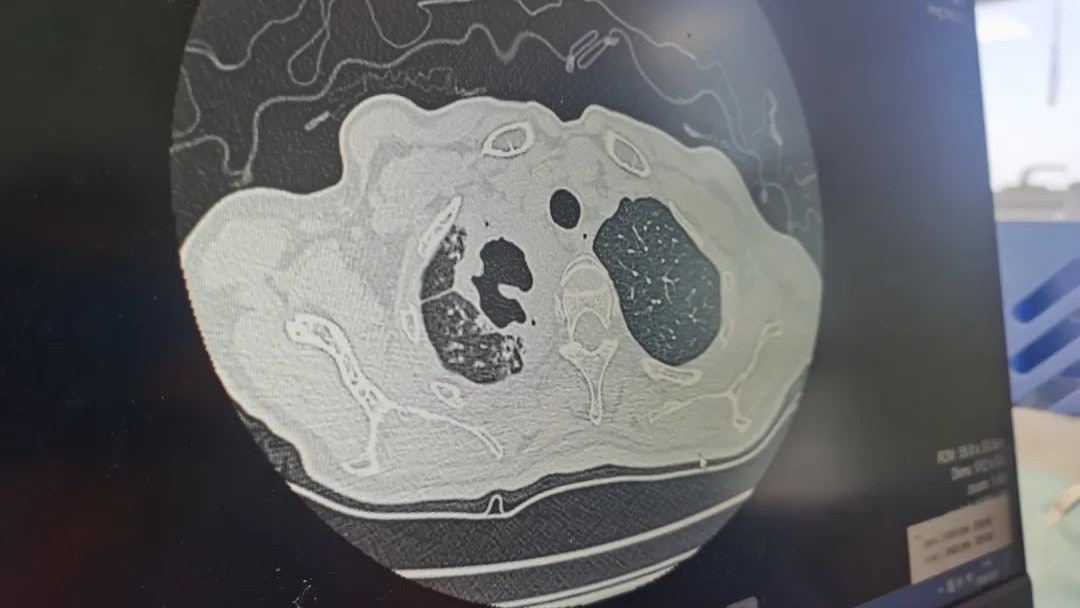

肺结核是由主要攻击肺部的结核杆菌引发,这种细菌在患者咳嗽或吐痰时,可通过空气传染。